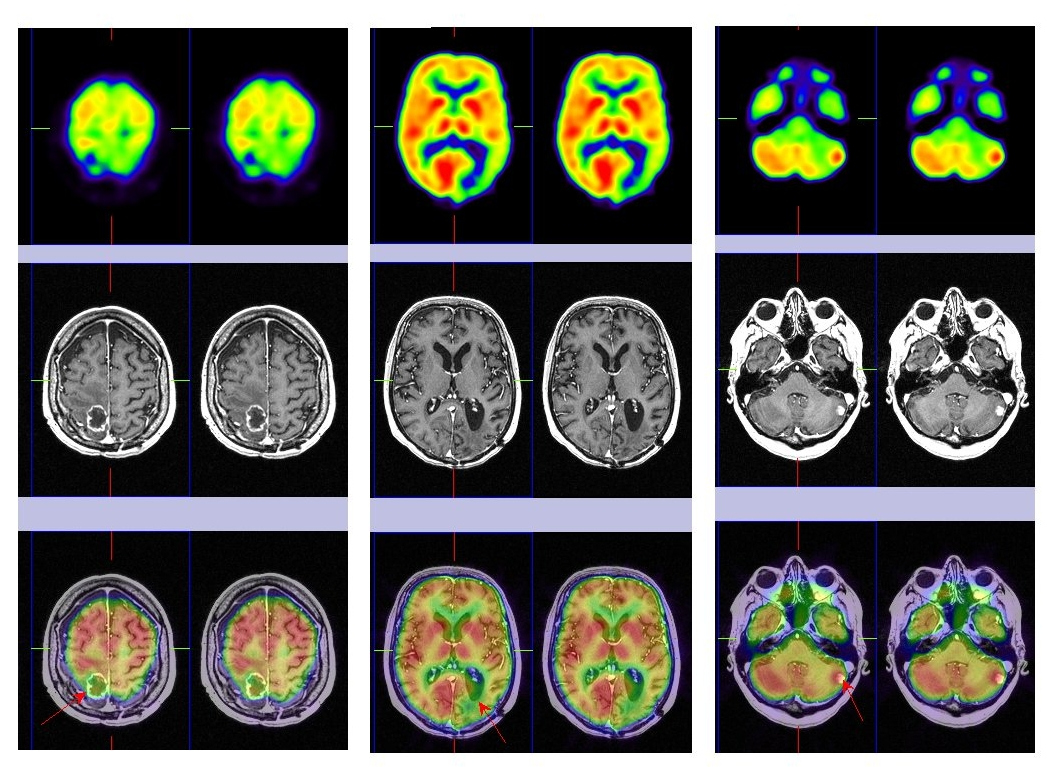

Al cabo de 5 meses la paciente refiere cefaleas y hemiparesia izquierda, realizándose una RM de urgencia que detecta un crecimiento de la lesión parietal derecha con realce periférico, captación heterogénea de contraste y edema perilesional, no mostrando cambios significativos las otras dos lesiones parieto-occipital y cerebelosa izquierdas. Se decide realizar un estudio PET-RM cerebral de control (fig. 2), donde se observa captación patológica de la 18F-FDG en la lesión aumentada de tamaño en lóbulo parietal derecho, que refleja recidiva tumoral y sin cambios en las restantes lesiones conocidas (radionecrosis).